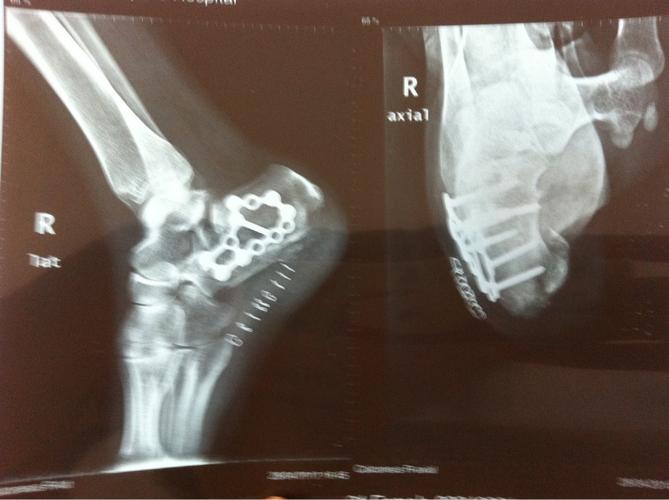

男42岁,跟骨骨折

请问我的这种跟骨粉碎性骨折如何康复才能最大的降低创伤性关节炎的

跟骨骨折病例分享

跟骨骨折87天了专家们给看看!